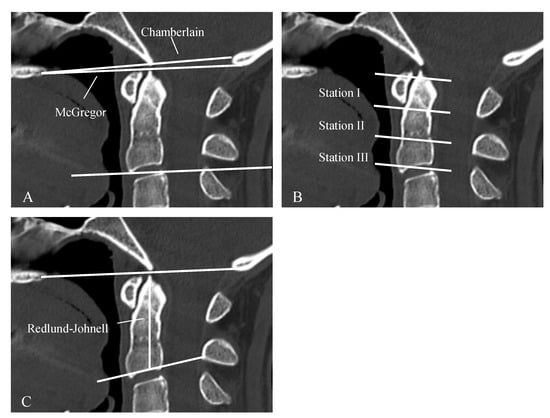

| CS (Cranial Settling) | vertical translocation of dens into the foramen magnum | see Figure 1 and Figure 2 |